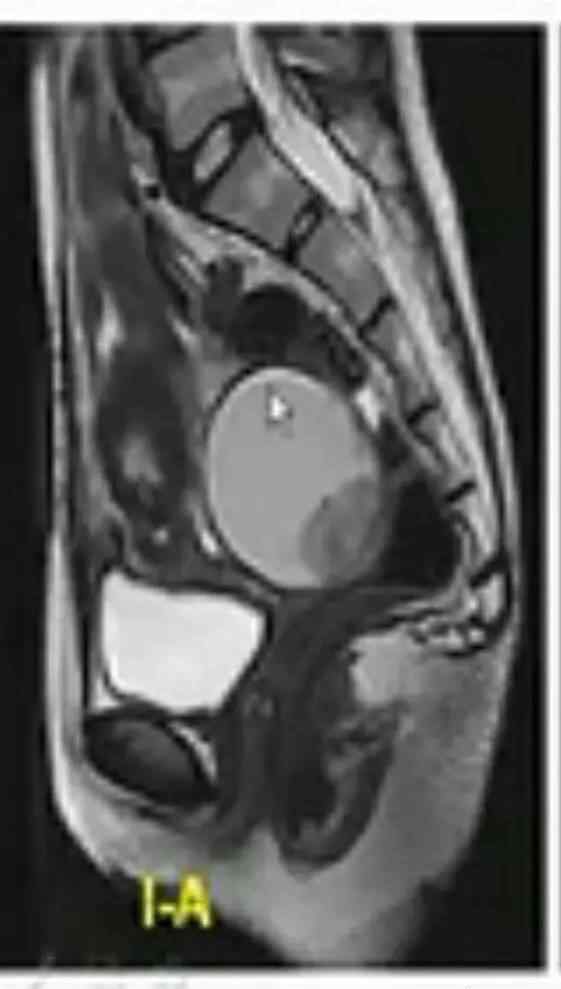

该病例的特征为腹膜后肿瘤、Tiwi+FS信号、液-液平面、T2WI+FS高信号、动态增强减影无强化

病理结果:异位支气管囊肿可见平滑肌细胞纤毛柱状上皮

最后我们总结一下:1。异位支气管囊肿:先天性,多见于腹膜后左侧,圆形/类圆形,薄壁单间,壁强化,t1信号强度相等或稍高,T2信号强度高,液面高。2.囊性畸胎瘤常见于女性新生儿左侧,呈圆形/类圆形,薄壁,单房或多房,壁无强化,成分复杂不均匀,也有脂肪分层。3.儿童囊性淋巴管瘤,生长在任何位置,薄壁,有或无间隔,均匀,低信号强度的钛和高信号强度的T2。4.中肾管/副中肾管囊肿年轻女性,圆形或类圆形。单间/多间,墙略厚且均匀,ti低信号,T2高信号。可能有激素刺激异常史。5.淋巴囊肿、泌尿囊肿、血肿、脓肿。有外伤史,泌尿系囊肿多见于肾脏周围。这些病变有各种形状,取决于病变的位置、性质和内容,并有相关病史。